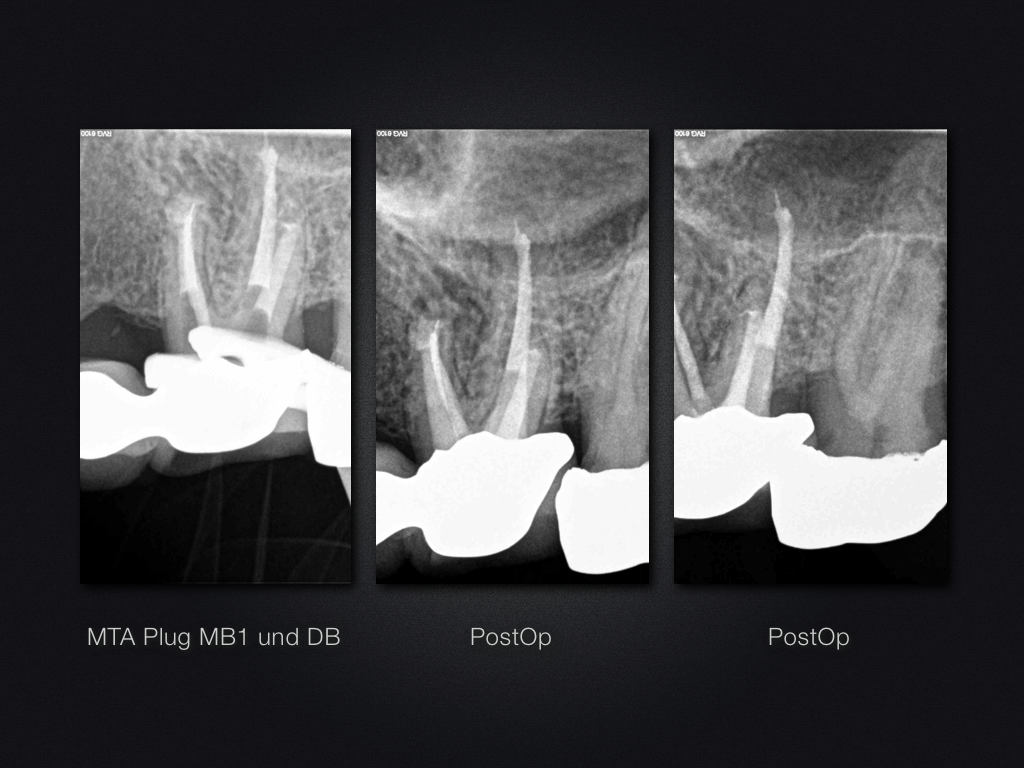

26D.011 Veröffentlicht 3. Juli 2013 am 1024 × 768 in Und wenn mein einziges Werkzeug ein Hammer ist, …